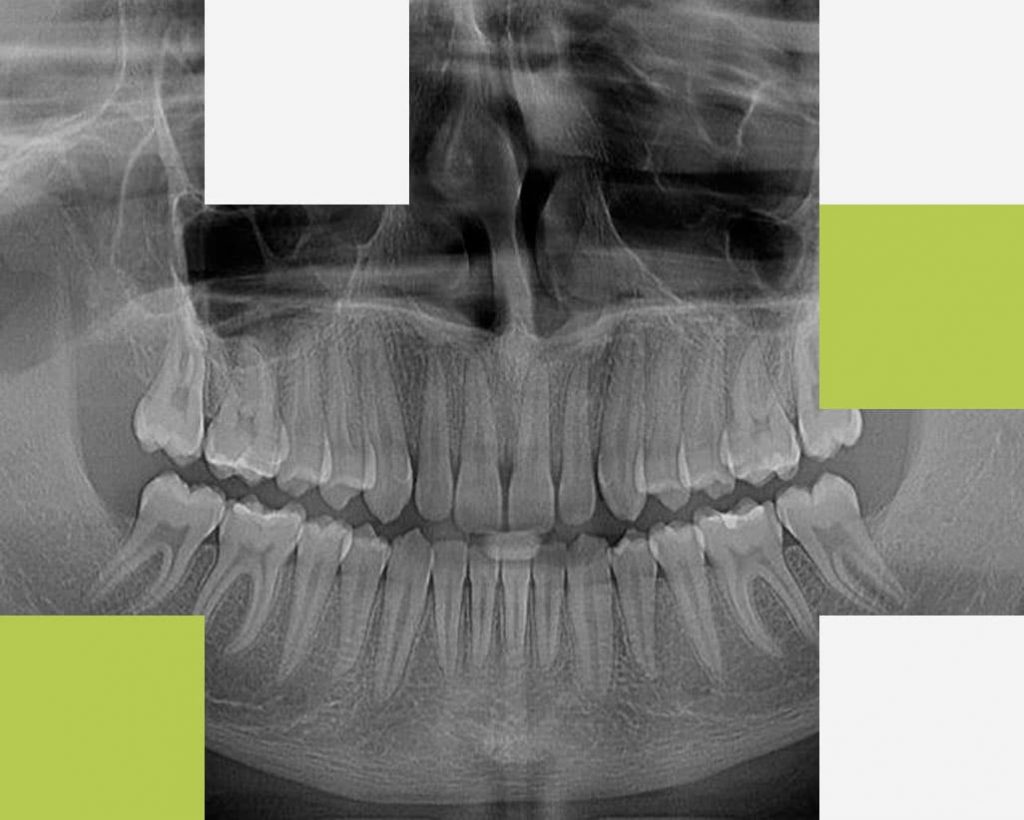

1. Radiografia digitală panoramică

Radiografia panoramică (Ortopantomografia) furnizează medicului o imagine de ansamblu a dentiției și a elementelor anatomice maxilo-faciale înconjurătoare. Această radiografie se realizează înainte de orice tratament stomatologic, astfel încât medicul să aibă o imagine completă a cazului pe care îl tratează, să evalueze posibile leziuni inflamatorii sau dinți neerupti, structura osoasă de susținere, articulațiile temporo-mandibulare, să vizualizeze molarii de minte, rapoartele dinților cu repere anatomice învecinate (nerv alveolar, sinus maxilar) sau posibile fracturi osoase maxilare sau mandibulare.